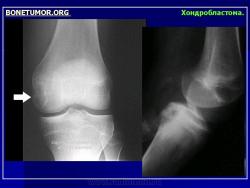

Хондробластома — это редкая доброкачественная опухоль, локализующаяся, главным образом, в эпифизе и отличающаяся своеобразным клеточным составом. Ткань новообразования представлена овальными, округлыми и веретеновидными клетками, напоминающими незрелые хондроциты (хондробласты). Зрелый гиалиновый хрящ определяется лишь в некоторых опухолях. Возраст больных варьирует. Мужчины поражаются в два раза чаше женщин. Пациенты предъявляют жалобы на боли в течение нескольких месяцев или лет, у некоторых больных определяются внутрисуставной выпот, припухлость и ограничение движений. Наиболее типичная локализация опухоли — проксимальные эпифизы плечевой и большеберцовой костей, а также дистальный эпифиз бедренной кости. У 20 % больных опухоль развивается в плоских или коротких трубчатых костях, преимущественно в пяточной и таранной. Изредка поражаются кости лицевого черепа, в том числе височная. В большинстве случаев новообразование выходит за пределы эпифиза и распространяется на метафиз. На фоне остеолиза обнаруживаются рассеянные участки обызвествления в виде пунктирных линий, а также разреженный трабекулярный рисунок. Хондробластома, как правило, не выходит за пределы кости, но изредка проникает в полость сустава. В процессе роста опухоли иногда возникает вторичная аневризматическая костная киста.

Рентгенологически хондробластома представляет собой сравнительно большой (2-4 см) очаг округлой формы, четко отграниченный от окружающей кости склеротической каймой. На фоне очага в большинстве случаев, но не обязательно определяются плотные включения, напоминающие хлопья ваты.

Рентгенологическая картина. Хондробластома выглядит как небольшой, от 3 до 6 см литический очаг, центрально или эксцентрично расположенный, с четкими контурами, занимающий около половины площади эпифизарной зоны. Хондробластома плоских костей и мелких трубчатых костей больших размеров, может сопровождаться припухлостью мягких тканей, вздутием кости и периостальной реакцией. Распространение процесса на метафизарную зону встречается часто.